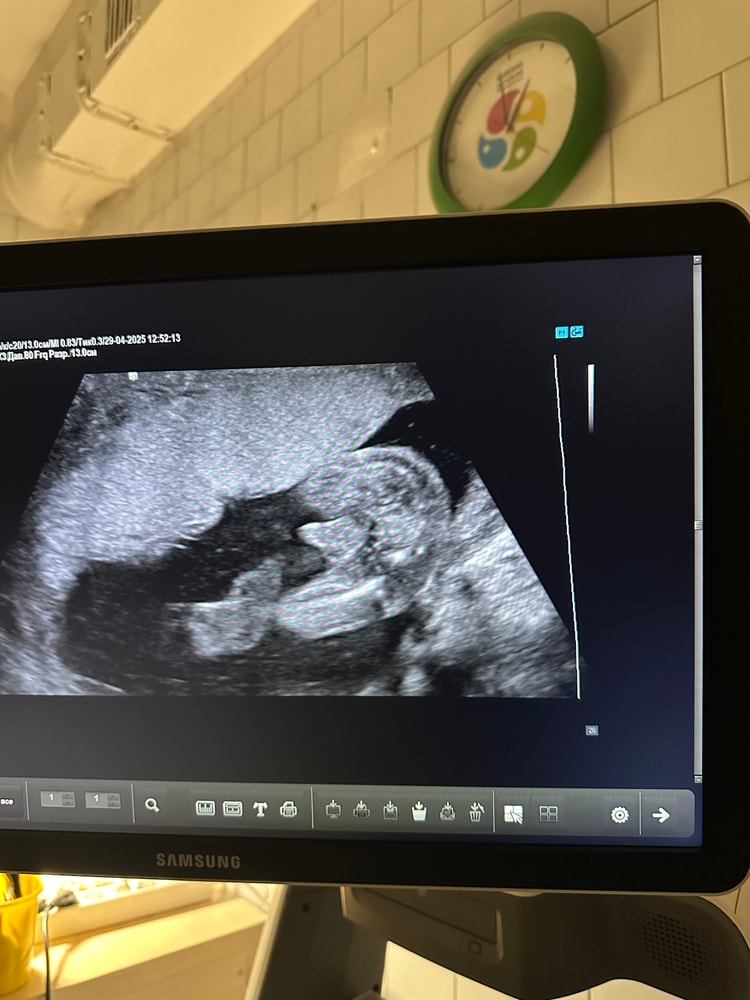

Вот так выглядит мальчик на 2 скрининге. У вас точно девочка Изображение

На 2 скрининге уже прекрасно все видно. У Вас девочка

Девочка

Ну, тут явно мальчукового ничего нет.